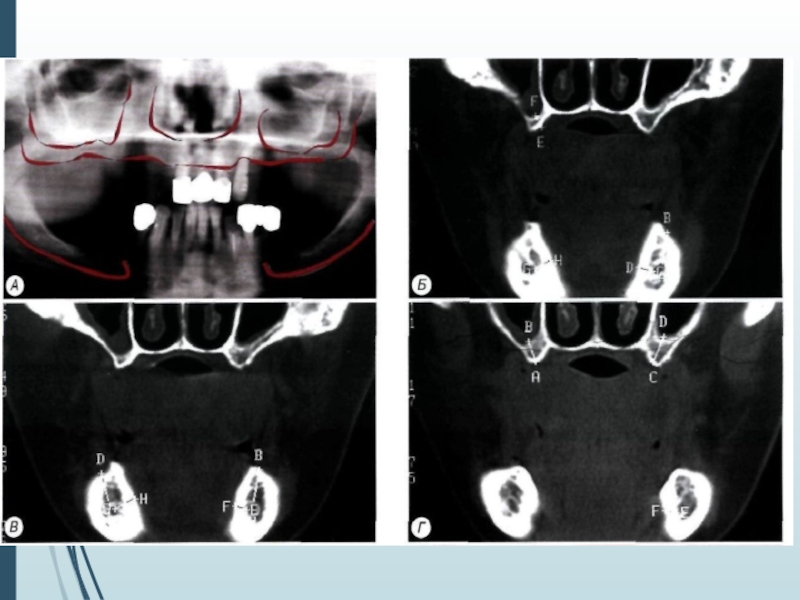

Слайд 13Компьютерная томография является одним

из наиболее информативных методов рентге-

нологического

обследования. С высокой степенью достоверности она

позволяет определить высоту и

ширину кости,

топографию нижнечелюстных каналов и верх-

нечелюстных пазух, особенности архитектони-

ки различных отделов челюстей, соотношение

последних, а также создать трёхмерное изоб-

ражение лицевого отдела черепа

Компьютерная томография является одним из наиболее информативных методов рентге- нологического обследования. С высокой степенью достоверности она позволяет